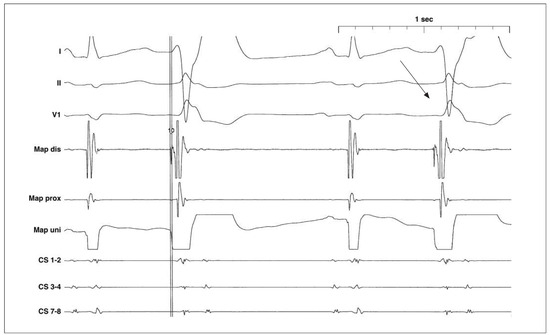

- Es fällt auf, dass die VES eine Rechtsschenkelblock(RSB-)Morphologie aufweisen (Rr’ in V1, tiefe und breite S-Zacken in I und V6). Daher ist von einem linksventrikulären Ursprung der VES auszugehen [1].